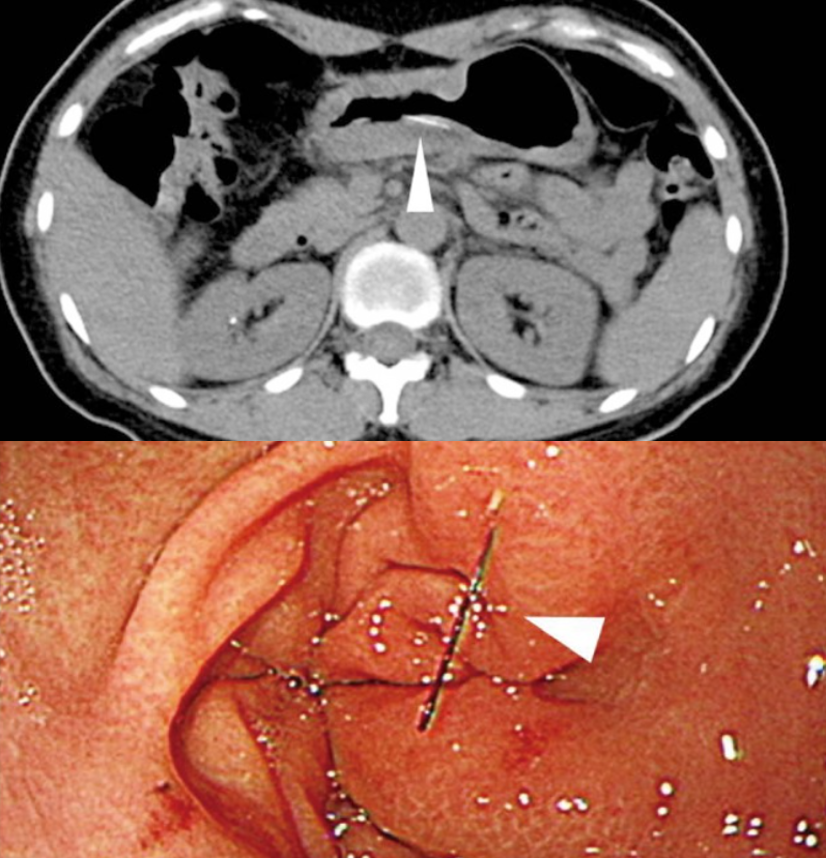

미국과 유럽 중심의 NEJM에서는 침 관련 영상이 자주 특이 케이스로 올라오지만, 한국에서는 아주 평범한 경우다. 그래도 침을 맞고 복강 내 감염음 좀 심했다. 전신 마취하에 농양 제거술을 받아야 한다.

복부.png <침이 위를 뚫은 경우>

침으로 인한 기흉은 매우 흔하고, 세균 감염으로 인한 봉와직염도 자주 본다. 심지어 위 내시경에서 침이 나오는 경우도 있다.